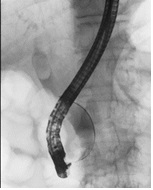

総胆管結石に対する内視鏡による排石術

総胆管にある結石